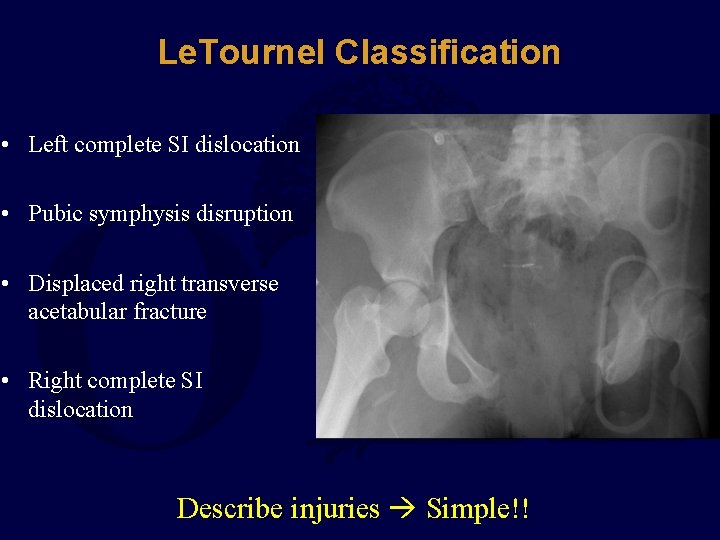

Le. Tournel Classification • Left complete SI dislocation • Pubic symphysis disruption • Displaced right transverse acetabular fracture • Right complete SI dislocation Describe injuries Simple!!